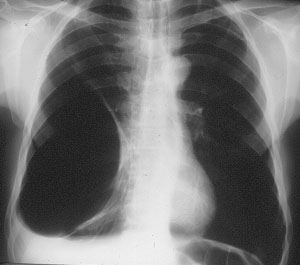

Group III: multiple bullae with underlying lung diffusely emphysematous (Figure 2)

| Figure 1: Operative view at thoracotomy of a single bulla with normal underlying lung. | Figure 2: Operative view at thoracotomy of multiple bullae with underlying lung with diffuse emphysema. |